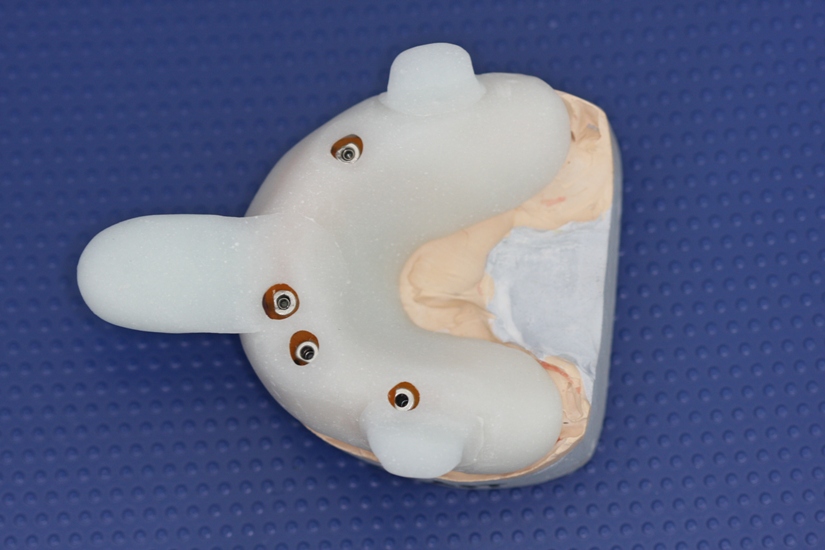

A temporary removable dental prosthesis was made at the stage of preparation

for the operation (Photo 3).